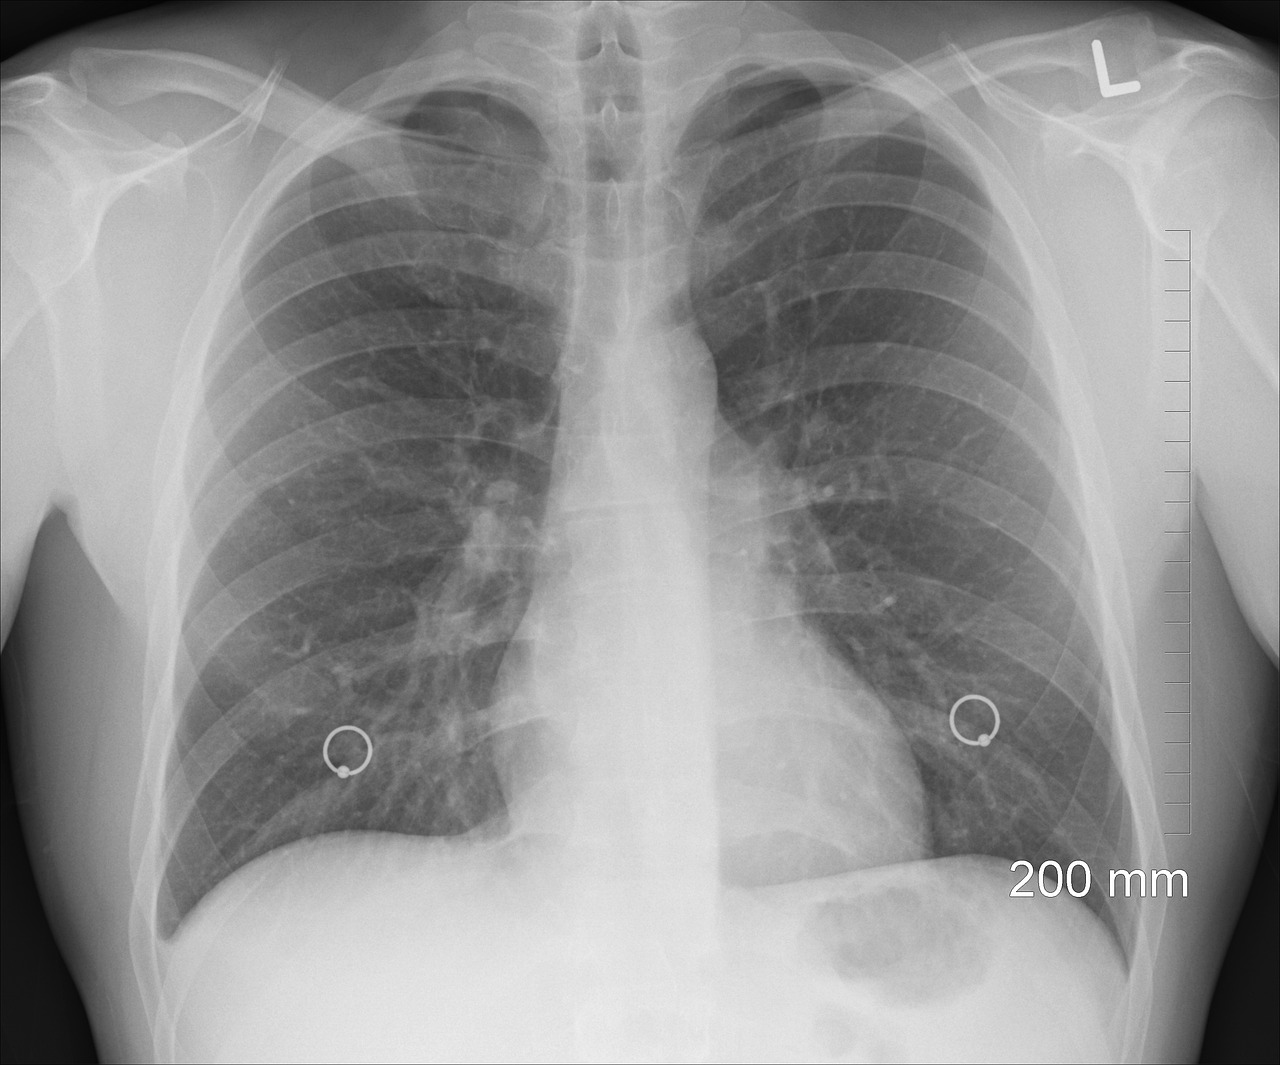

① 흉부 X선 촬영

X선 검사방법으로는 실제 크기로 촬영하는 흉부 직접촬영과 70㎜, 100㎜ 크기의 축소된 사진으로 찍는 간접촬영이 있는데, 여러 사람을 집단으로 검사할 경우에는 간접촬영을 많이 이용합니다.

소견에 따라 초감염 결핵과 재활성화 결핵으로 나뉘며 흔히 전자는 소아 결핵, 후자는 성인 결핵으로 분류하기도 하며 인체면역결핍 바이러스(HIV) 감염자는 초감염 결핵 소견이 주로 나타나는 것으로 알려져 있습니다.